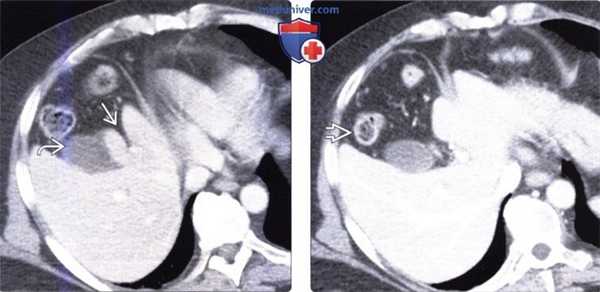

(Слева) На аксиальной КТ с контрастным усилением определяется в значительной степени уменьшенный в размерах медиальный сегмент печени, расположенный между щелью серповидной связки и желчным пузырем. Передние сегменты также уменьшены в размерах.

(Справа) На аксиальной КТ с контрастным усилением в этом же случае визуализируются толстая кишка и жировая клетчатка сальника, заполняющие промежуток между правой и левой долей печени у пациента с врожденной гипоплазией переднего и медиального сегментов.

(Слева) На аксиальной КТ с контрастным усилением определяется гипоплазия переднего и медиального сегментов. Обратите внимание на клипсу после ранее выполненной холецистэктомии (в норме желчный пузырь располагается между долями печени). Также обратите внимание на грыжевое выпячивание желудка и толстой кишки латерально и в краниальную сторону.

(Справа) На более каудальном аксиальном КТ срезе без контрастного усиления у этого же пациента визуализируется свободное пространство, обусловленное врожденной гипоплазией переднего и медиального сегментов печени, заполненное жировой клетчаткой сальника и печеночным изгибом ободочной кишки.